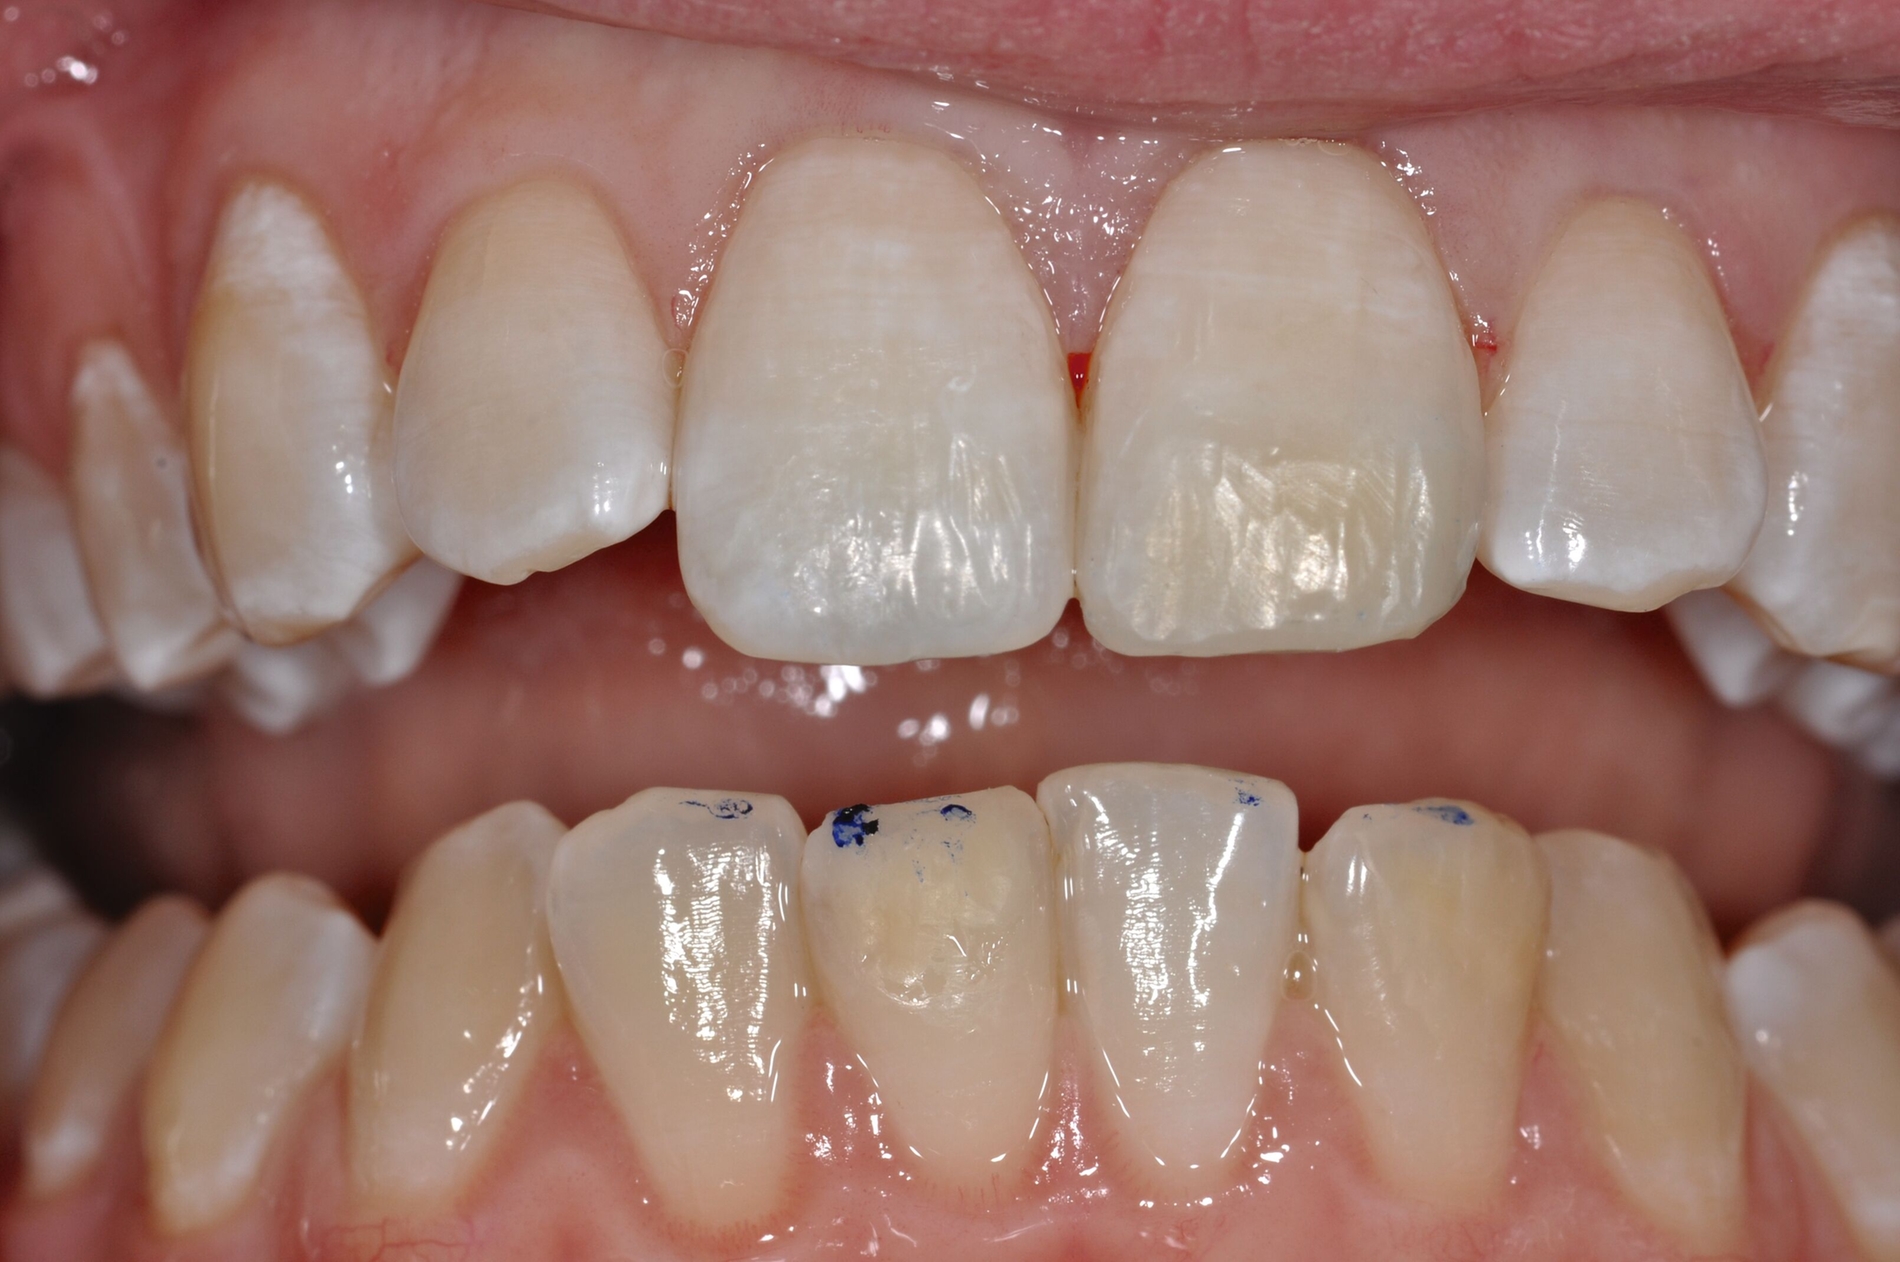

Diese Klassifikation dient als Grundlage für die Therapieempfehlungen. Deutlich wird, dass aufgrund der Symptomatik die Therapie der Zähne höchst unterschiedlich ausfällt. Dass etwa eine Opazität ohne Überempfindlichkeit (Index 1, Abbildung 1) ein anderes therapeutisches Vorgehen erfordert als ein Zahn mit nahezu komplettem Einbruch der Zahnoberfläche und mit Hypersensitivität (Index 4, Abbildung 2), ist offensichtlich.

Für die zahnärztliche Praxis gibt die Einteilung eine Orientierung darüber, welche Behandlungsmaßnahmen erforderlich sind beziehungsweise eingesetzt werden können. Je nach Schweregrad wird dabei zwischen nichtinvasiven und invasiven Maßnahmen sowie einer kurzzeitigen oder längerfristigen, restaurativen Therapie unterschieden. Bei der Überarbeitung des Konzepts wurde zudem zwischen Front- und Seitenzähnen differenziert (Abbildung 3) [Bekes et al., 2023; Steffen et al., 2017].

Die Versorgung der MIH-Frontzähne entspricht dem Vorgehen im Seitenzahnbereich. Problematisch ist die Maskierung der Opazitäten. Dazu müssen opake Komposite verwendet werden und es muss eine Schichtstärke von circa 1,5 mm garantiert sein (Abbildung 9).